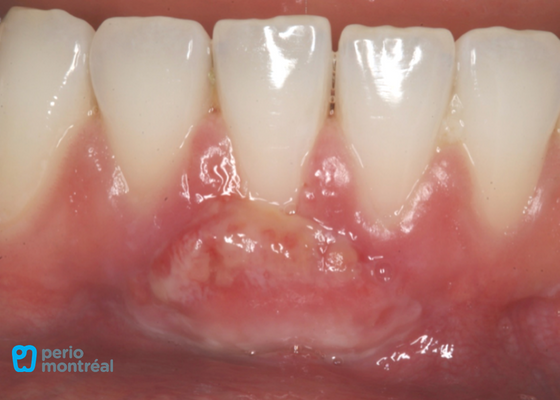

1 Week Post-Op

1 Month Post-Op